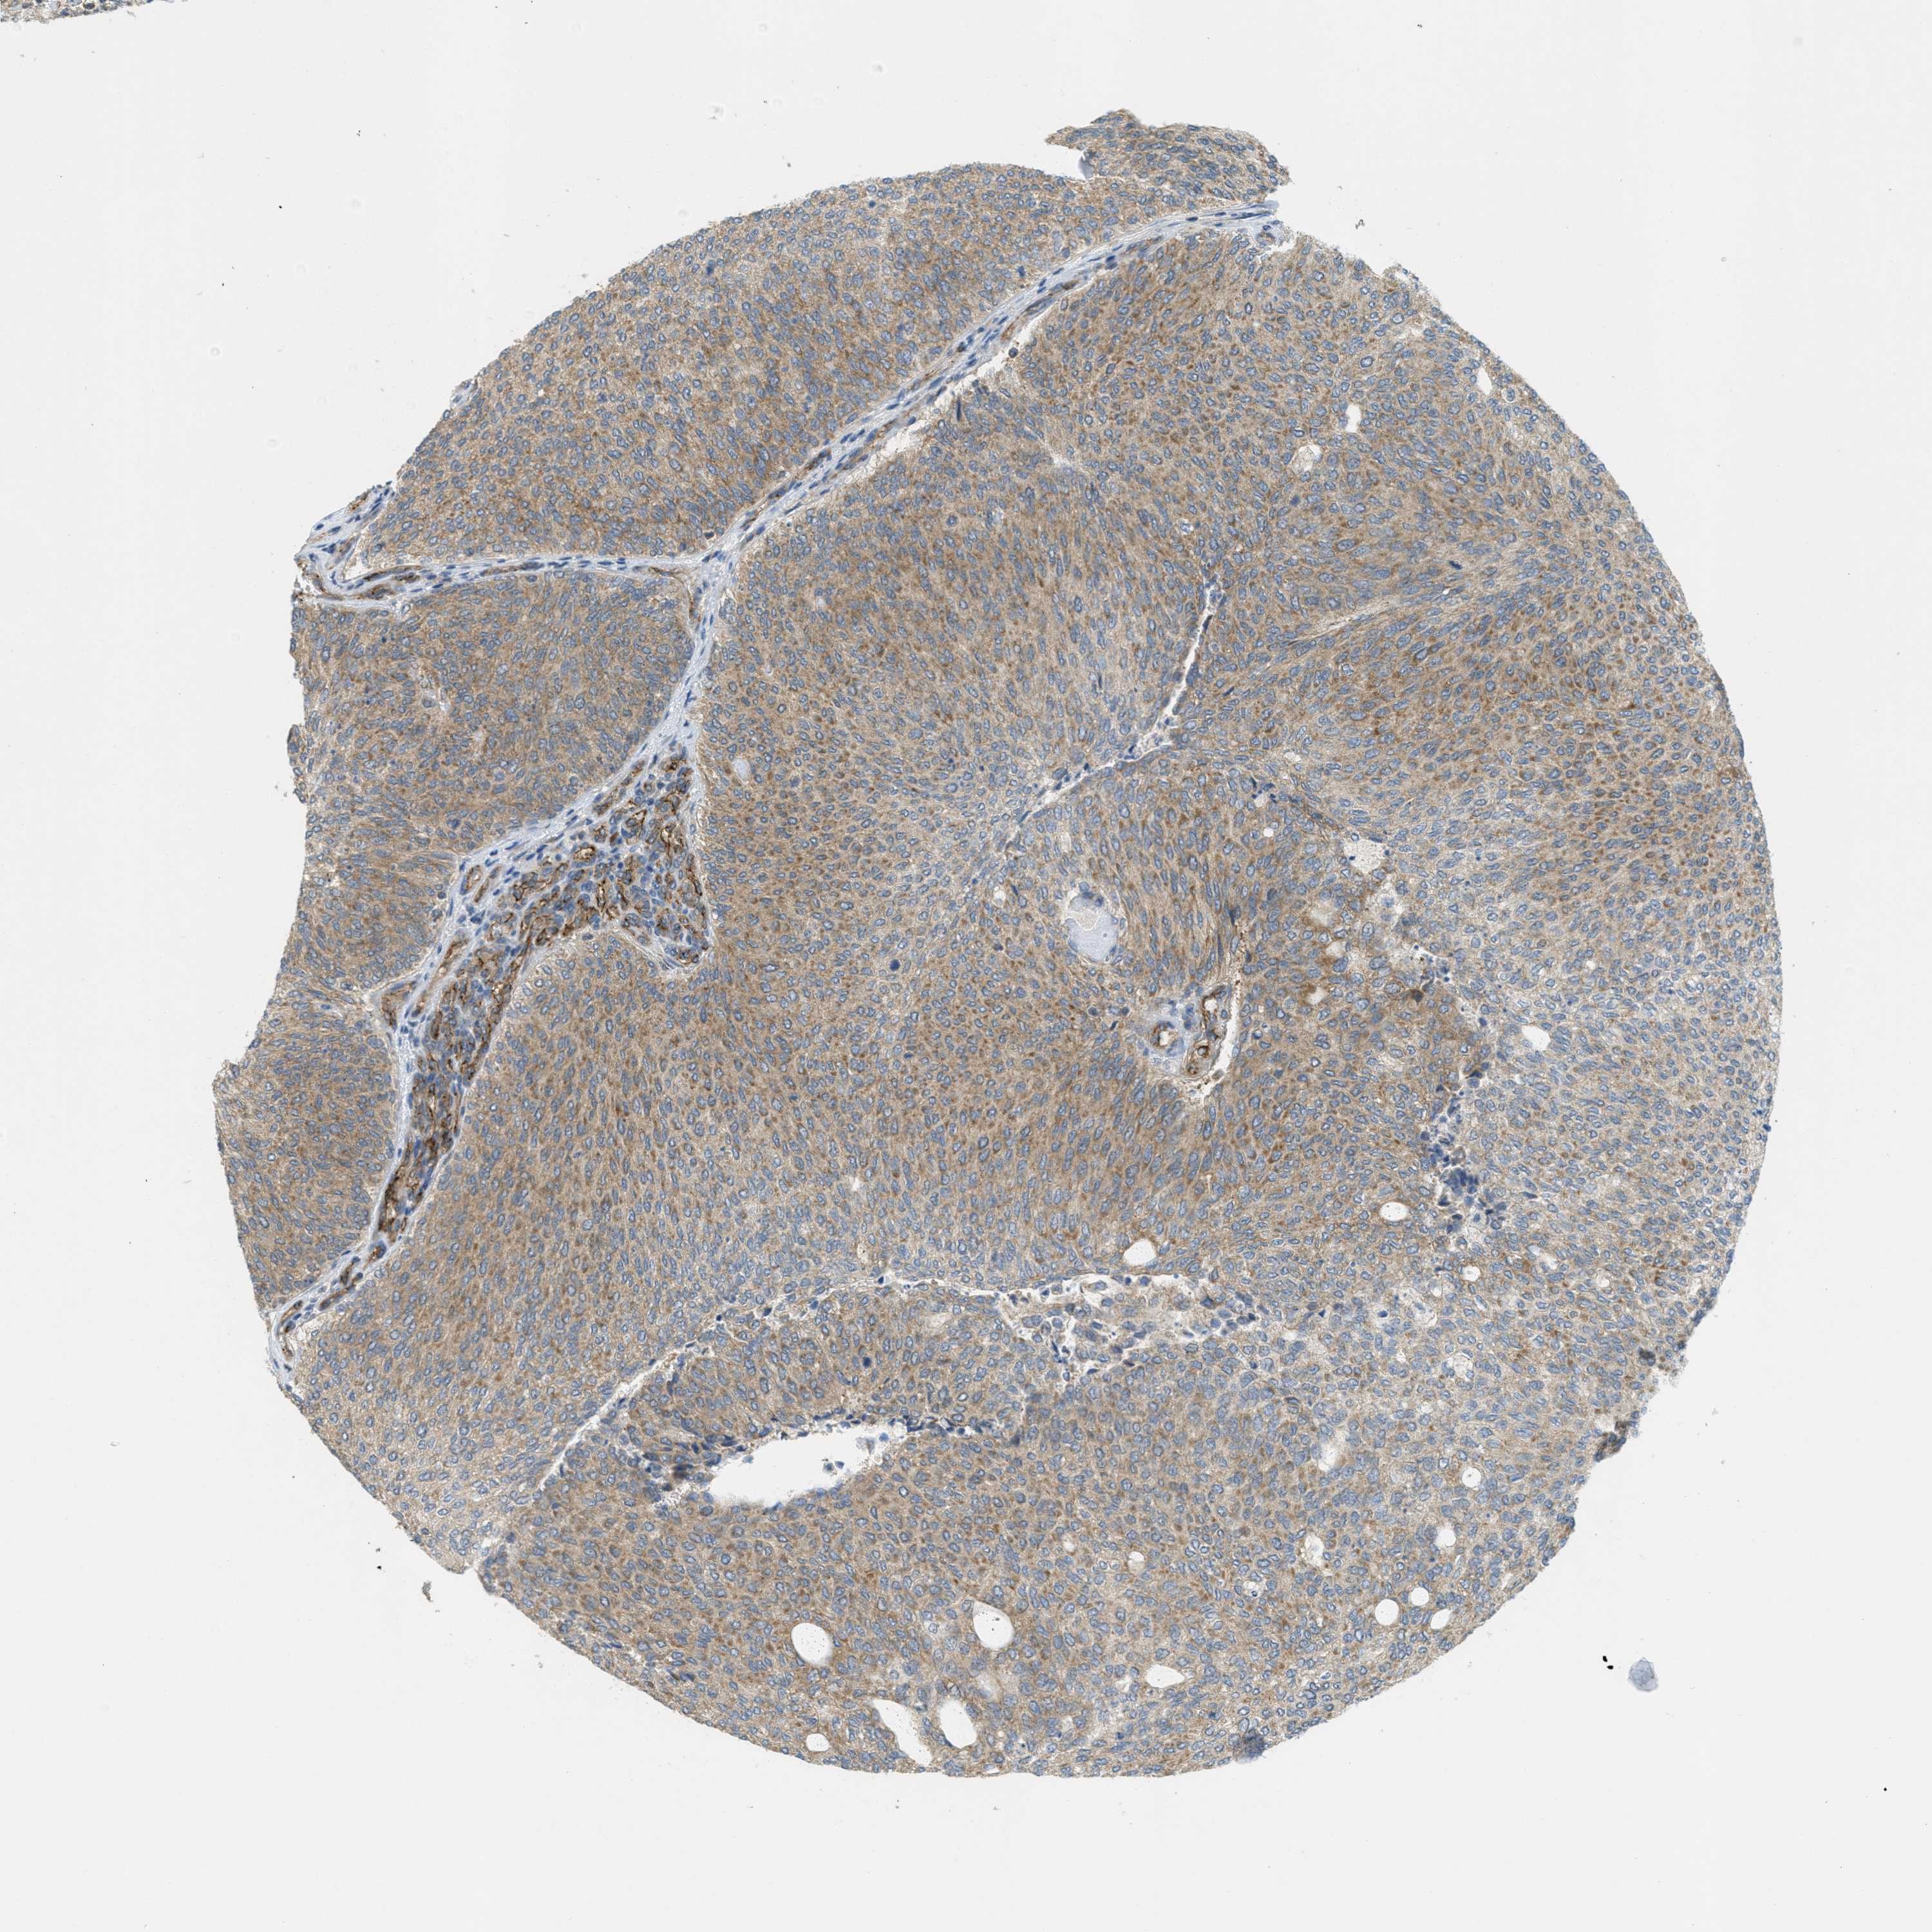

UROTHELIAL CANCER - Protein expressioni

A mouse-over function shows sample information and annotation data. Click on an image to view it in a full screen mode. Samples can be filtered based on level of antibody staining by selecting one or several of the following categories: high, medium, low and not detected. The assay and annotation is described here.

Antibody stainingi

Antibody staining in the annotated cell types in the current human tissue is reported as not detected, low, medium, or high, based on conventional immunohistochemistry profiling in selected tissues. This score is based on the combination of the staining intensity and fraction of stained cells.

Each image is clickable and will lead to virtual microscopy that enables deeper exploration of all samples and also displays staining intensity scores, fraction scores and subcellular localization as well as patient and tissue information for each sample.

Antibody HPA017956

Staining

High

Medium

Low

Not detected

Intensity

Strong

Moderate

Weak

Negative

Quantity

>75%

75%-25%

<25%

None

Location

Nuclear

Cytoplasmic/membranous

Cytoplasmic/membranous,nuclear

Urothelial carcinoma, Low grade

Urothelial carcinoma, High grade